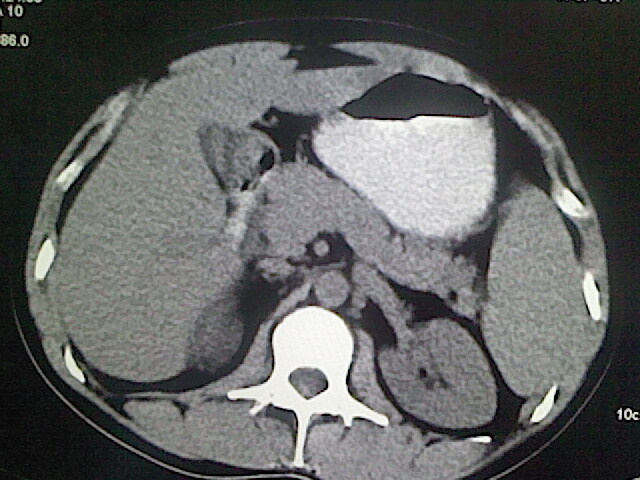

以下是引用卜一在2009-3-14 9:49:00的发言:[br]胆囊萎缩,胆囊壁不规则增厚,内部结构模糊,增强明显强化。另:肝左叶外侧段肝囊肿。支持:慢性胆囊炎!高度可疑:胆囊癌!

以下是引用余辉在2009-3-14 8:48:00的发言:[br]1)慢性胆囊炎。2)肝左叶外侧段肝囊肿。3)脂肪肝。[br]支持,胆囊萎缩,密度增高,不知b超具体有何提示,钙胆汁?结石?

以下是引用jiangjing在2009-3-14 10:18:00的发言:[br]1)慢性胆囊炎。2)肝左叶外侧段肝囊肿。3)脂肪肝。4.】建议行肝功能检查